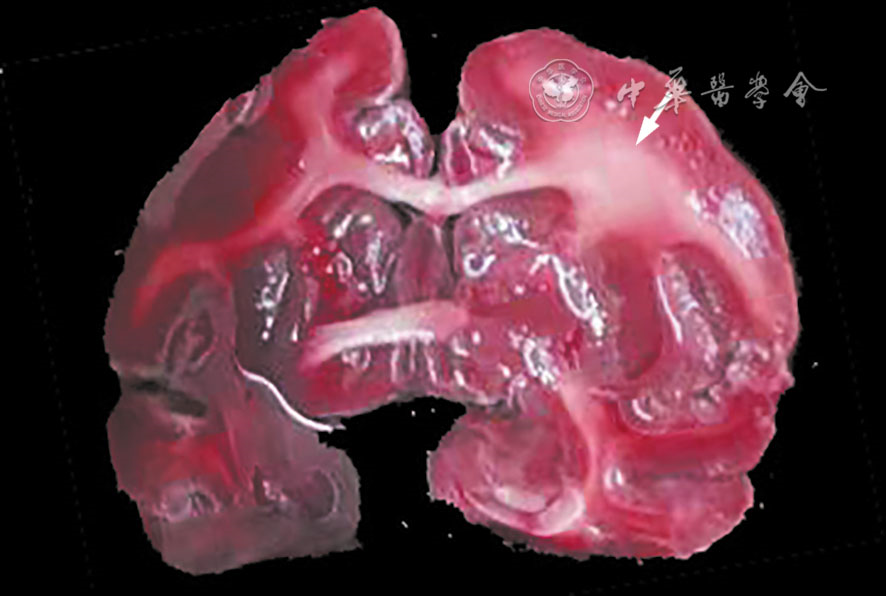

叶娟, 尚海龙, 沈海林, 等. DSA引导下食蟹猴大脑中动脉栓塞模型的建立与评价 [J]. 介入放射学杂志, 2022, 31(4): 369-373.

Yoshikawa T, Akiyoshi Y, Motokawa K, et al. Cerebral angiography and neurobehavioral patterns in a non-human primate middle cerebral artery occlusion model [J]. In Vivo, 2024, 38(5): 2245-2253.